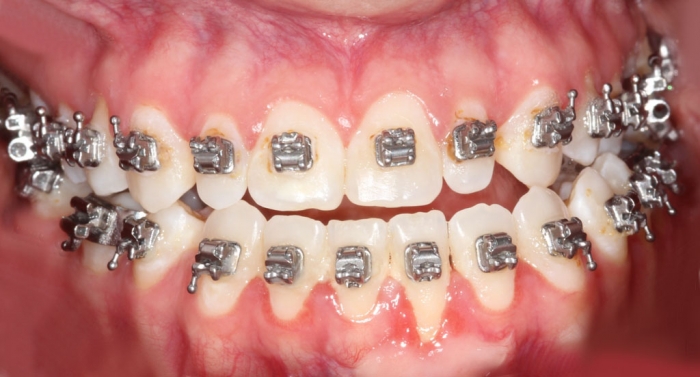

Mordida inicial - Clínica Cliniface

Mordida inicial

Mordida após a cirurgia - Clínica Cliniface

Mordida após a cirurgia